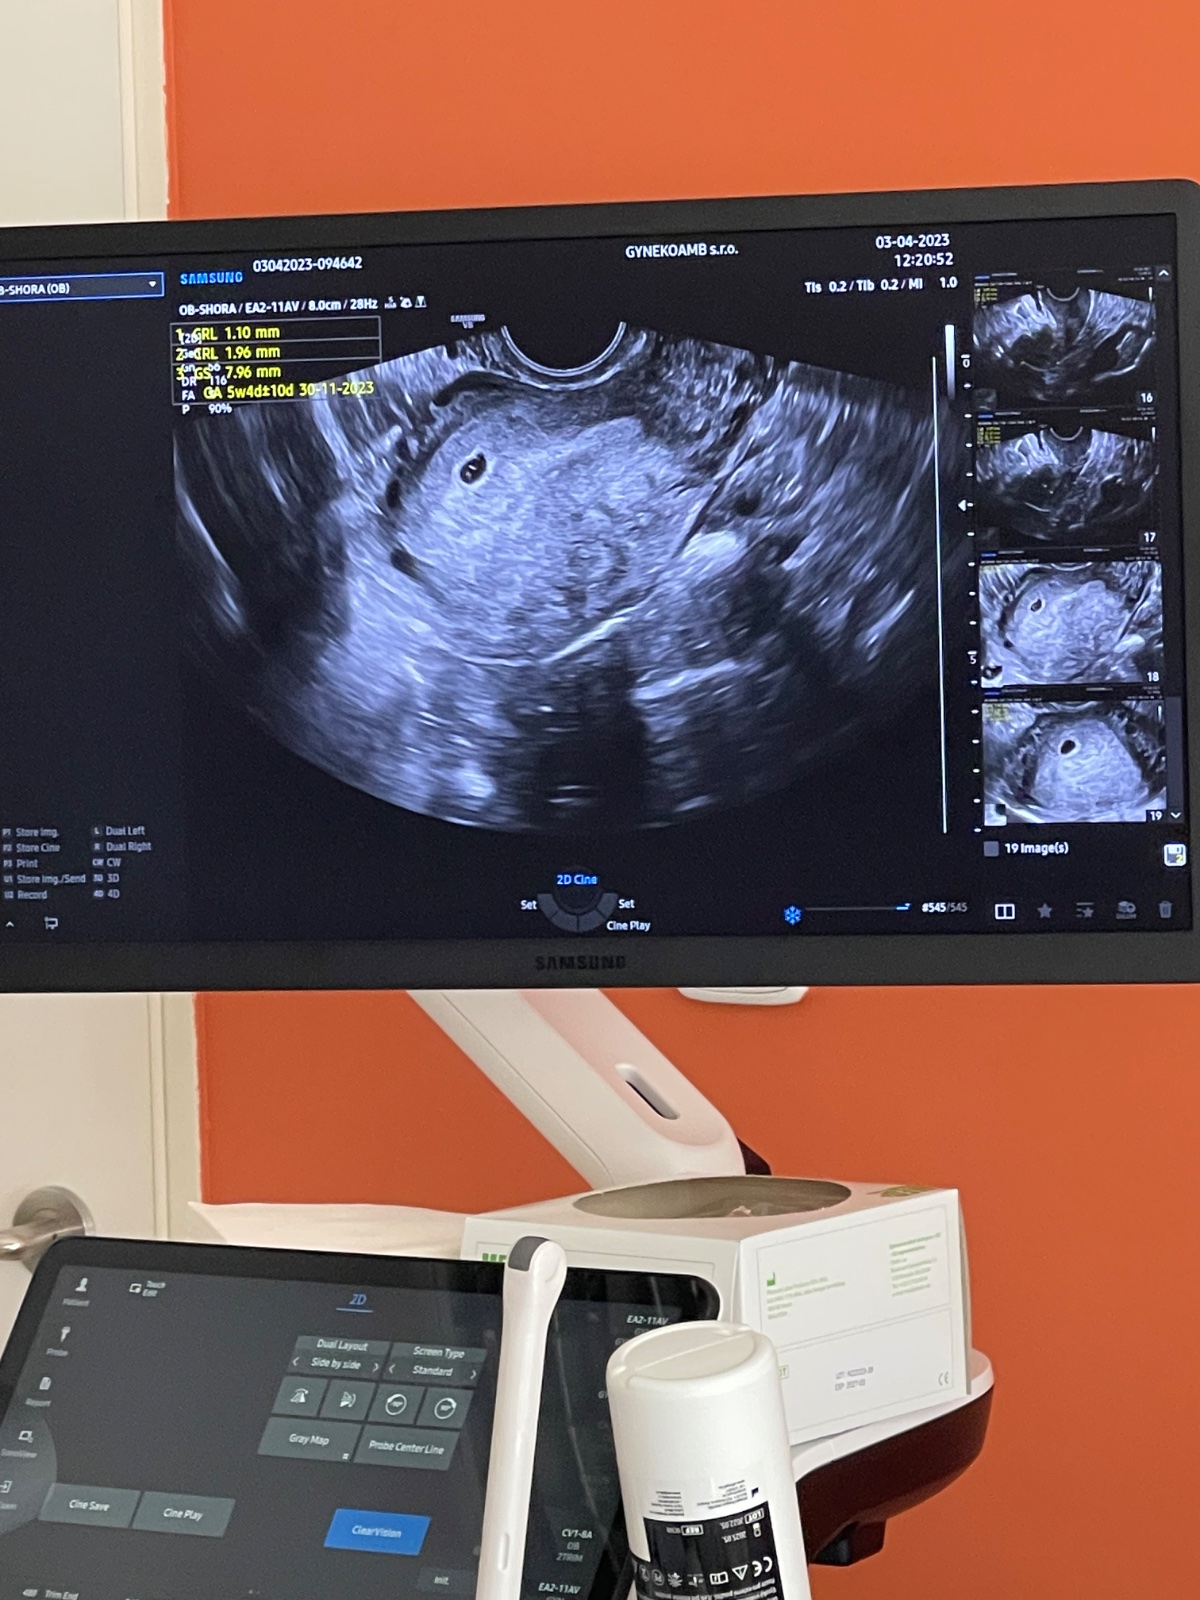

Ukážeme své ultrazvuky v pátém týdnu těhotenství?

u mě šel vidět v 5+3tt tt gestacni a žloutkový váček. Další kontrolu mám za tyden 8+1tt, tak už by mělo jít vidět víc 🍀

@lucajde vubec se nestresuj, ne nadarmo vetsina doktoru dela UTZ az kolem 8.tt. Me by ho ani nedelal, ale kvuli trombofilii a nutnemu predepsani injekci potreboval vedet brzy, ze se jedna o normalni a ne treba mimodelozni tehotenstvi. U tebe je taky videt v deloze, takze ucel UTZ v tak brzkem stadiu si myslim, ze se splnil 🙂👍🍀

Myslím že na 5. týden je to ok🙂 já byla v 5+6 (6tt) a bylo tam vidět srdíčko a takové pidi kolečko. Dřív jsem ale nebyla, takže to nevím🙂 podle mě tam má být aspoň dutinka, což tam je. Držím palce 🍀❤